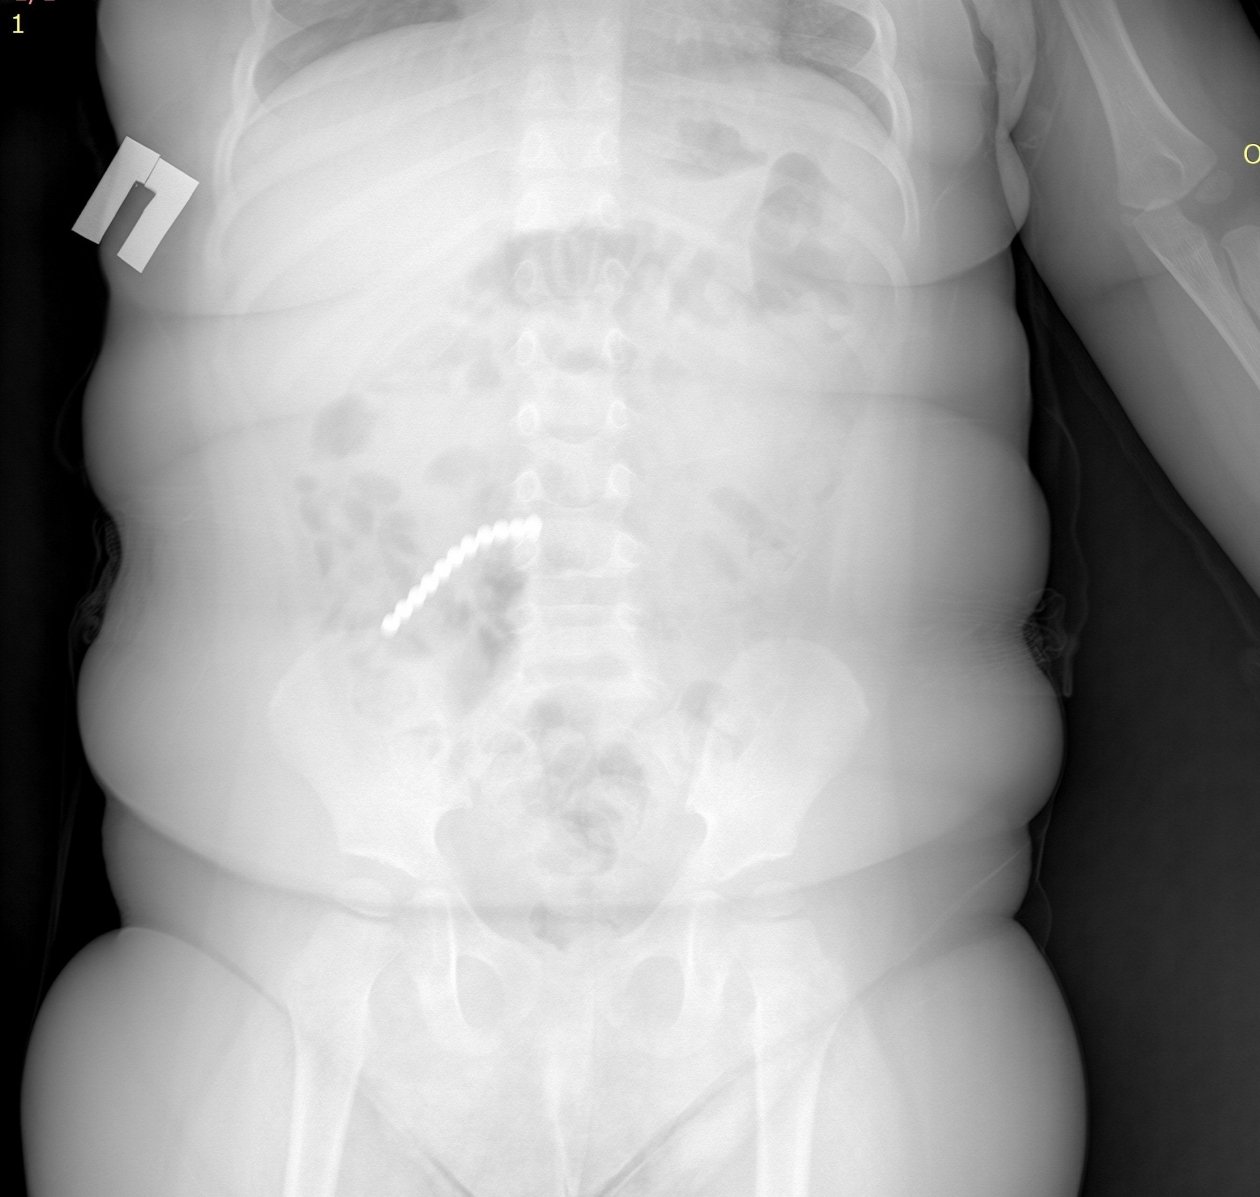

Ребёнок поступил в Приемно-диагностическое отделение ДРКБ в начале февраля с рвотой и ухудшением состояния. Рентген сразу показал десятки инородных тел в пищеварительном тракте — 20 магнитных шариков от неокуба. Врачи смогли извлечь 9 из них эндоскопически, но остальные переместились в кишечник и вызвали тяжелые осложнения.

Малыш в Бурятии проглотил 20 магнитных шариков. Фото: ДРКБ Бурятии